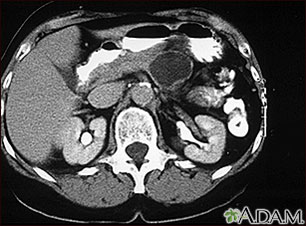

Esta TC del abdomen superior muestra, en la parte superior derecha de la imagen, un gran quiste en el páncreas (adenoma quístico del páncreas).